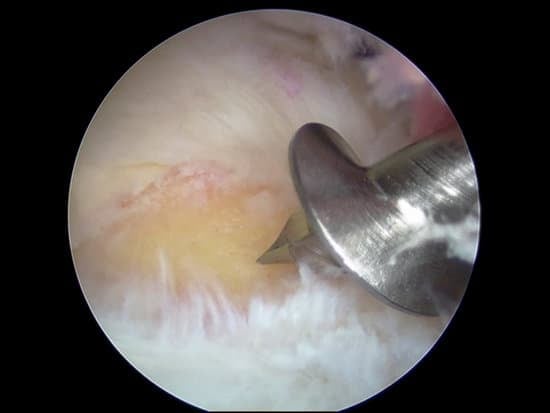

앵커(Anchor)는 어깨 관절경 수술에서 파열된 회전근개나 인대를 뼈에 견고하게 고정하는 데 사용됩니다.

사용 사례: 회전근개 파열의 복구 등에서 널리 사용됩니다.

어깨 관절경 수술에 사용되는 앵커는 재질, 형태, 고정 방식에 따라 다양하게 선택됩니다.

흡수성 앵커는 체내에서 분해되어 재수술 시 유리하며, 비흡수성 앵커는 강력한 고정력을 제공합니다.

수술 전, 환자의 상태와 필요에 따라 적절한 앵커를 선택하는 것이 성공적인 회복에 중요한 역할을 합니다.